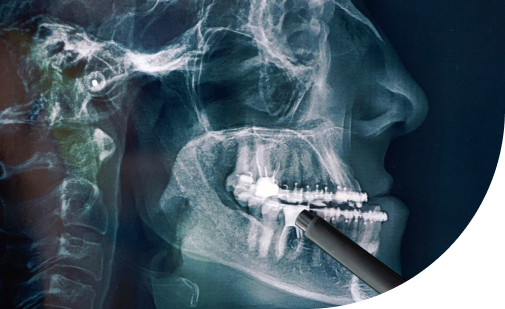

La especialidad de Maxilo facial se dedica al diagnóstico, prevención, tratamiento y rehabilitación de un amplio espectro de enfermedades, lesiones y defectos que afectan funcional y estéticamente la cabeza, el cuello, la cara, las mandíbulas y, por supuesto, la boca y los dientes.

La cirugía reconstructiva mayor, busca devolver la forma y la

función a pacientes que han perdido partes significativas de su

estructura facial y oral.

La reconstrucción de los huesos maxilares (maxilar superior y

mandíbula) y de la boca (tejidos blandos como la lengua o el

paladar) es un pilar de esta especialidad.